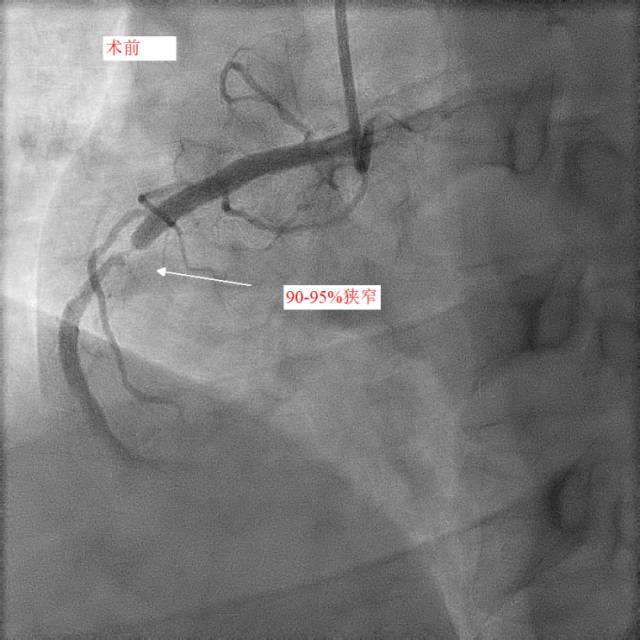

第二天,小天和父亲同一天接受冠脉造影和手术治疗,冠脉造影进一步明确了:小天冠状动脉回旋支完全堵死、前降支90%堵塞,而右冠状动脉也仅有一丝血流通过。造影中医生发现,小天的血管狭窄已经有一段时间,其中的右冠状动脉已经产生了侧支循环。随后医生在患者右冠状动脉里放入了两个支架,恢复了血流。